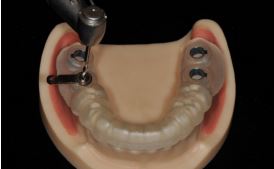

제가 그간 소개해 드렸던 임상 케이스를 보면

이렇게 투명한 장치 사진을 간혹가다

보신 적이 있을 겁니다.

바로 이게 ‘가이드’라 불리는 것이죠.